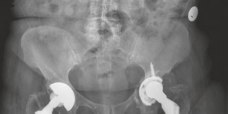

Initial radiographic evaluation consisted of standardized, weight-bearing anteroposterior (AP) and lateral views of the right hip, alongside a full-length AP pelvis radiograph to assess bilateral symmetry, pelvic obliquity, and offset.

The AP Pelvis radiograph demonstrated catastrophic failure of the index arthroplasty. There was evidence of severe, expansile acetabular osteolysis, predominantly localizing to DeLee and Charnley zones 1 (superior) and 2 (medial). The uncemented acetabular shell exhibited significant superior and medial migration, with apparent protrusion of the medial wall into the true pelvis. A continuous, wide radiolucent line (>2 mm) was visible at the bone-prosthesis interface, confirming gross aseptic loosening. The teardrop was obliterated, and the Kohler's line (ilioischial line) appeared compromised, raising the clinical suspicion for an uncontained medial defect or impending pelvic discontinuity.

Based on the comprehensive imaging suite, the acetabular defect was classified as a Paprosky Type IIIB. This classification signifies severe superior migration (>3 cm), massive volumetric bone loss, an incompetent superior dome, and a teardrop that is frequently destroyed or significantly altered, yet with the maintenance of pelvic continuity. The femoral defect was classified as a Paprosky Type III, characterized by extensive metadiaphyseal bone loss with intact diaphyseal bone distal to the isthmus, capable of providing initial mechanical stability for a revision stem.

Clinical & Radiographic Imaging